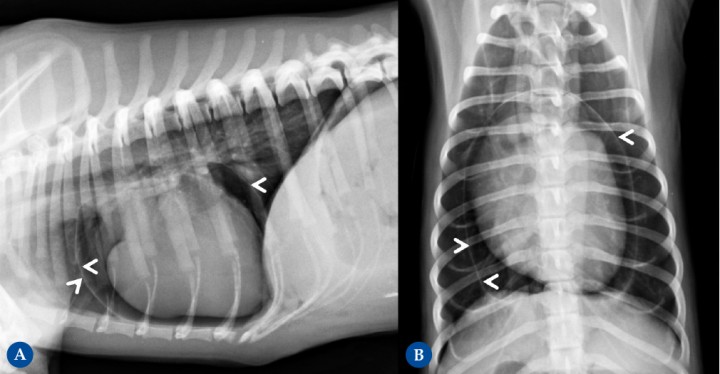

<p>(<strong>A</strong>) Proyección lateral derecha. (<strong>B</strong>) Proyección ventrodorsal. Conviene recordar que en radiografía se valora el conjunto de la silueta cardíaca, que incluye el miocardio, pericardio y líquido pericárdico. Paciente con neumopericardio iatrogénico tras resolución quirúrgica de una hernia peritoneo-pericárdico diafragmática. Se identifica una fina línea de opacidad tejido blando (cabezas de flecha) creando una bolsa alrededor del corazón en ambas proyecciones radiográficas. Entre esta línea y el corazón se identifica un contenido de opacidad gas, lo que permite diferenciar con mayor claridad las cámaras cardíacas. En condiciones fisiológicas, en el espacio pericárdico se localiza una mínima cantidad de líquido, todo ello de opacidad tejido blando, por lo que no permite diferenciar los distintos componentes y por eso se determina como silueta cardíaca.</p>

Figura 12

(A) Proyección lateral derecha. (B) Proyección ventrodorsal. Conviene recordar que en radiografía se valora el conjunto de la silueta cardíaca, que incluye el miocardio, pericardio y líquido pericárdico. Paciente con neumopericardio iatrogénico tras resolución quirúrgica de una hernia peritoneo-pericárdico diafragmática. Se identifica una fina línea de opacidad tejido blando (cabezas de flecha) creando una bolsa alrededor del corazón en ambas proyecciones radiográficas. Entre esta línea y el corazón se identifica un contenido de opacidad gas, lo que permite diferenciar con mayor claridad las cámaras cardíacas. En condiciones fisiológicas, en el espacio pericárdico se localiza una mínima cantidad de líquido, todo ello de opacidad tejido blando, por lo que no permite diferenciar los distintos componentes y por eso se determina como silueta cardíaca.